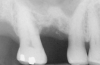

The 2-mm twist drill is used to create an osteotomy 1 mm short of the subantral floor. If any resistance is detected prior to reaching the 3-mm depth, drill penetration must be stopped, because the subantral cortical bone has possibly been reached. Any uncontrolled "push" would penetrate the bone and likely perforate the sinus membrane. A guide pin is then inserted and a radiograph taken to determine if drill penetration has terminated within 1 mm of the subantral floor (Figure 2). If the radiograph indicates that more than 1 mm of bone is present subantrally, the twist drill is used again to penetrate within 1 mm of the sinus floor. Alternately, an osteotomy tip for a piezosurgery unit can be used for this purpose. The final depth of penetration should be verified with another periapical film.

Figure 2  After drilling to a depth of 3 mm with a 2.1-mm twist drill, the guide pin was placed and a radiograph was taken to ascertain if the drill stopped within 1 mm of the subantral floor.

Figure 2